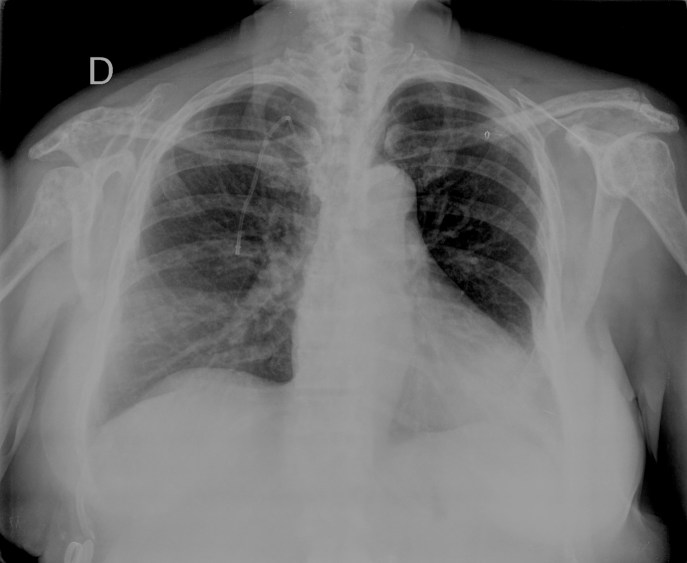

- En un principio podríamos decir que existe un aumento de densidad retrocardiaco que podría ser compatible con condensación neumónica a dicho nivel, sin embargo estamos ante una placa poco inspirada, lo cual puede llevarnos a cometer errores diagnósticos.

- Se recomendó volver a realizar la radiografía, observar a continuación:

Ya no se observa el aumento de densidad retrocardiaco, la placa es normal.

INSPIRACIÓN: Una placa bien inspirada es aquella en la que se observar 6-7 arcos costales anteriores o 10-11 arcos costales posteriores. Lo contrario puede producir imágenes falsas de condensaciones o de seudocardiomegalia.